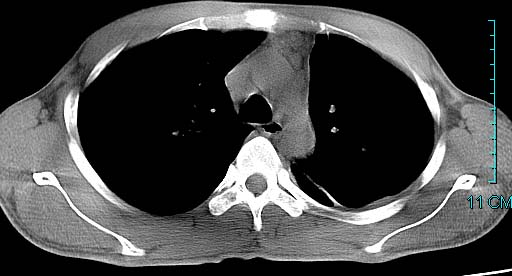

以下是引用ctkz987在2006-3-28 13:04:00的发言:[br]左侧胸腔积液穿刺后多发气液平(多房性),结合临床有高热不除外合并感染。

以下是引用qian在2006-3-28 14:32:00的发言:[br]左肺下叶大片状阴影,密度不均,见有条片影和空洞及气液平,少量胸腔积液伴有胸膜增厚,从图像看积液密度比水的密度高,结合病史,考虑左下肺化脓性炎症伴有脓胸。

以下是引用wawaquan在2006-3-28 22:25:00的发言:[br]左上肺舌段多发斑片影。结合“男24y咳嗽咳痰气促伴高热(38.5--39.5)20多天”及穿刺史,[br]考虑1 左下肺化脓性炎症;2脓胸。

以下是引用乡医在2006-3-28 18:37:00的发言:[br]左侧多发液气平面结合患者男24y咳嗽咳痰气促伴高热(38.5--39.5)20多天,查胸水:ldh239.3,总蛋白59.19,tb-ab阴性,利凡它试验+,红c2.7*109,白c1.08*109,分类淋巴92%分叶8%,考虑1脓胸2肺隔离征感染